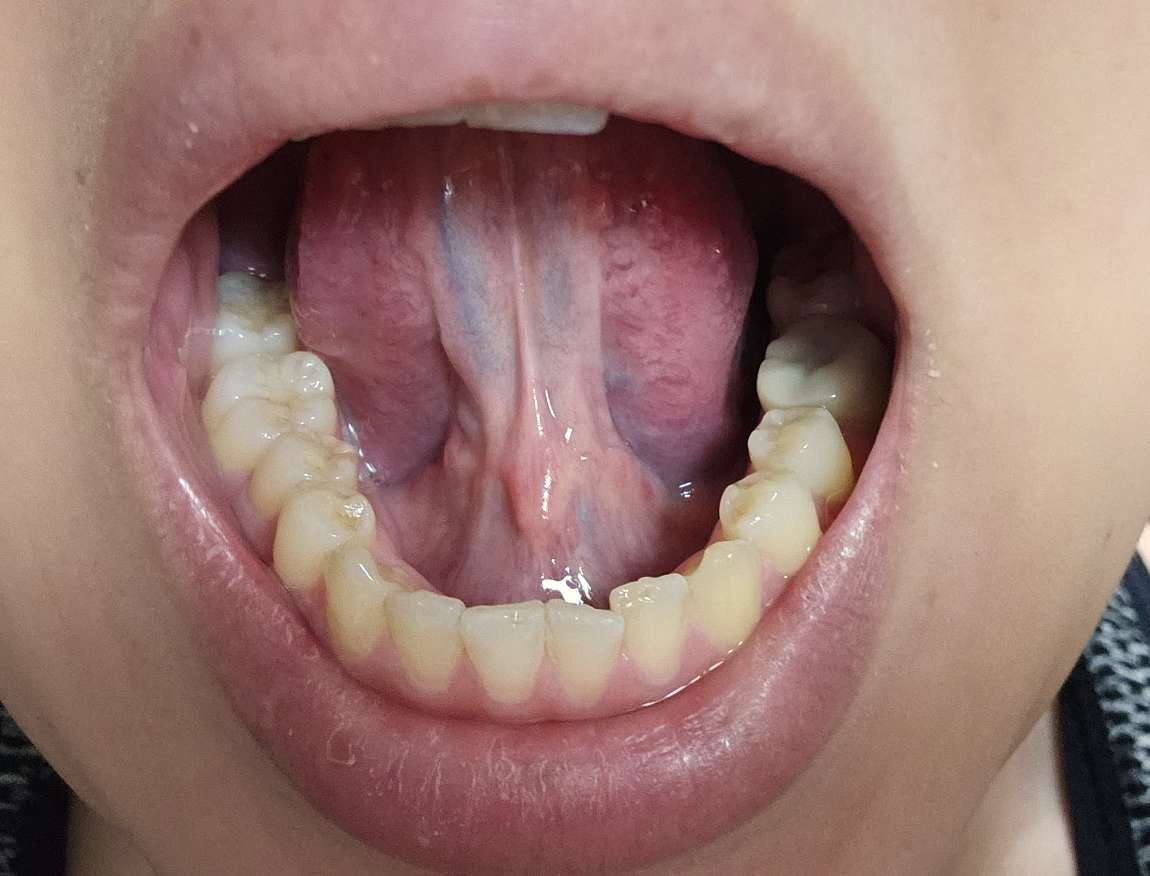

自身で舌も見たところ

似たような長めの突起が複数確認できました。

画像1Compress_20251118_194448_8847.jpg 画像2Compress_20251118_194645_5638.jpg